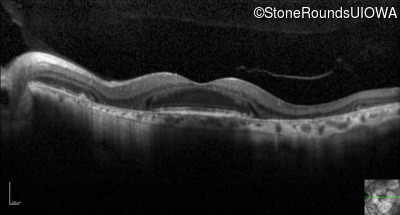

Optical Coherence Tomography - Left - 20/50

Exemplar / OCT Stack